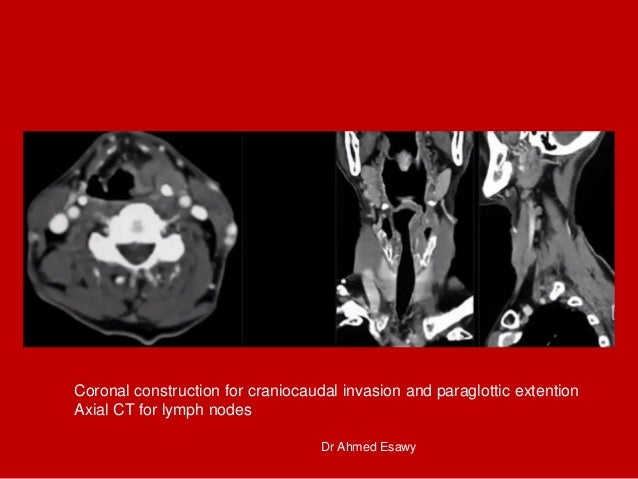

14. 14. Coronal construction for craniocaudal invasion and paraglottic extention Axial CT for lymph nodes Dr Ahmed Esawy